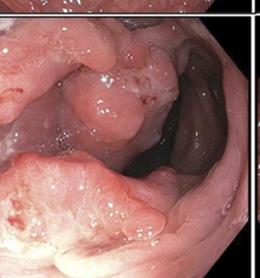

Okay, we thought, so It's not their department. Is it the gastroenterologists’ domain? When I went public with my cancer story, I did an interview with physician Dr. Jon LaPook. He said to me that many times when a colonoscopy is performed, the scope goes through the rectum and anus and doesn't include them in the exam. They're missed. Deeply confused, I looked up the gastroenterologist’s scope of practice and read, “a gastroenterologist is a specialist with expertise in the disorders and diseases that affect the digestive system. Which includes the gastrointestinal tract, esophagus, stomach, small intestine, large intestines, rectum, and anus as well as the pancreas, liver, bile ducts, and gallbladder.” Why did he tell me to make sure to tell the doctor to turn the camera around? So, I looked up what the colonoscopy was supposed to examine, and I found that during routine colonoscopy screenings for colon cancer doctors are looking for abnormalities or diseases in the colon, and don't usually examine the anus. I was stunned. What?! So where does that leave us? Or rather, the neglected anus? My hope today is that you will take on this fight for the anus and give it the attention it deserves.